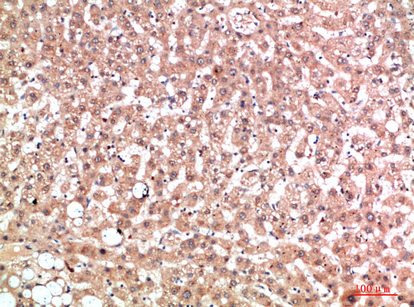

IHC 1/50-300 Human,Mouse,Rat